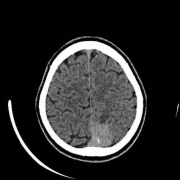

脑肿瘤 能活多久?对于脑肿瘤以及颅内占位性病变等神经外科疾病...